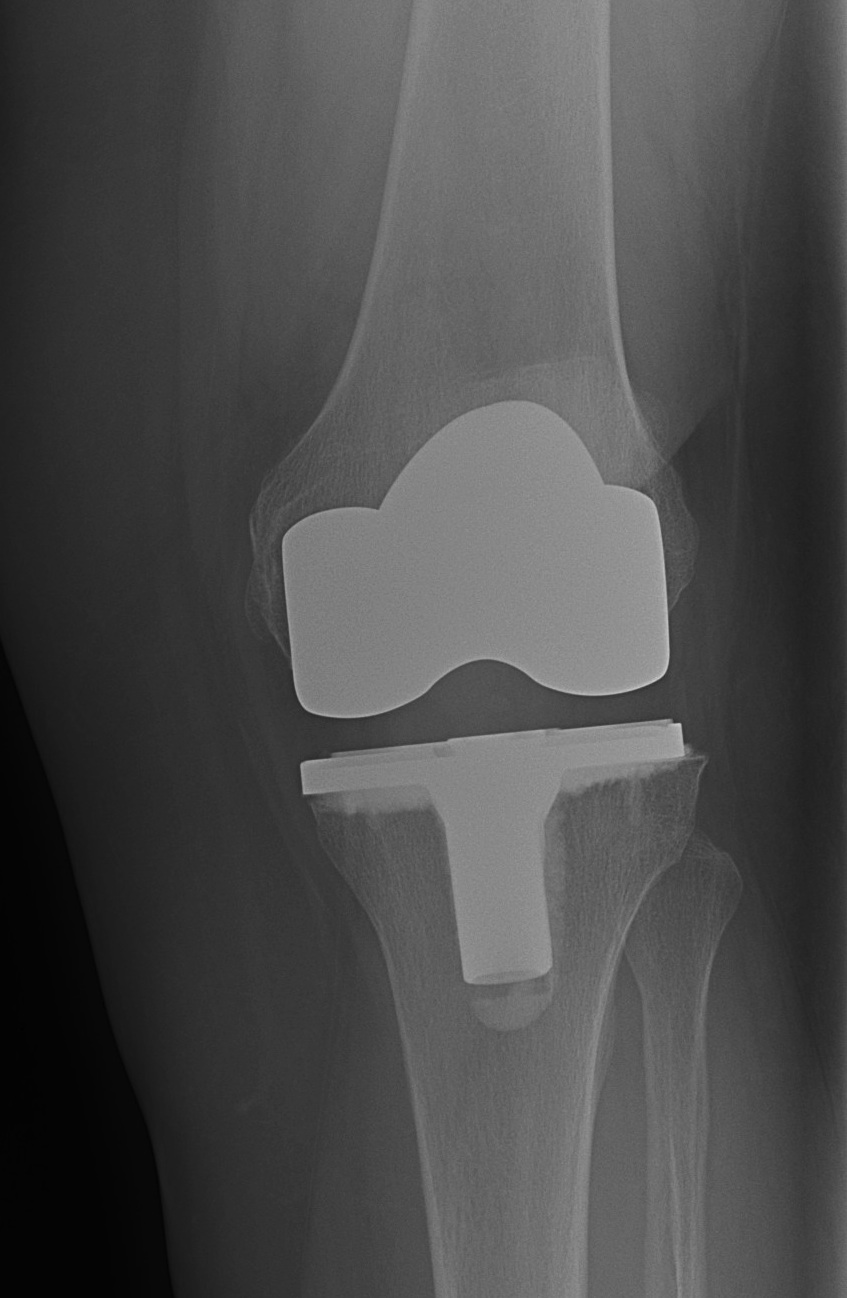

Malalignment

Post operative mechanical limb axis within a range of 180 +/- 3o

- associated with lower rates of aseptic loosening

Creates a net varus or valgus moment

- excessive stress on one side of the knee

- excessive wear

- early failure